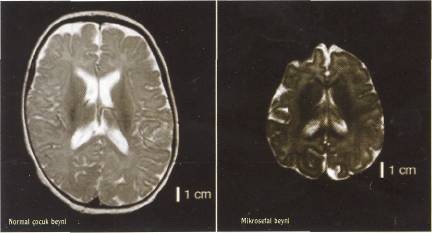

Lahn yönetimindeki araştırmacılar, çalışmalarını mikrosefalın ve ASPM diye adlandırılan iki gen üzerinde odaklamışlar. Bu genler, birincil mikrosefali denen ve normalden çok küçük beyinlerle kendini gösteren bir anormal durumdan sorumlu. 443Lahn'ın ekibi ve başka gruplar daha Önceki çalışmalarında mikrosefalin ve ASPM'nin insana özgü türlerinin insanlarla şempanzelerin ayrılmasından sonra yoğun bir doğal-seçilim baskısı altına girdiklerinize böylece insanların beynindeki olağanüstü büyümeden sorumlu olduklarını göstermişti. İlk atalarımızın evrimine daha başka genlerin de katkıda bulunduğu zaten biliniyor. Lahn ve ekip arkadaşları, yeni araştırmalarında seçilimin mikrosefalin ve ASPM üzerinde modern insanların ortaya çıkmasından sonra da devam ettiğinin kanıtlarını aramışlar. Bunun için, ABD'de Coriell Tıp Araştırmaları Enstitüsü'nde saklanan ve insanların tüm genetik çeşitliliğini temsil eden 90 hücrenin DNA dizilimlerini oluşturmuşlar. Araştırılan her iki gen için de İnsan topluluklarında şaşırtıcı bir sıklıkla ortaya çıkan bir avantajlı alel bulmuşlar. Alel, aynı genin bir anneden, biri de babadan gelen kopyalarına deniyor. İstatistik testleri, bu sıklığın rastlantısal genetik kayma ya da nüfus göç-

İnsanlar olarak büyük beyinlerimizle gurur duymakta haksız değiliz. Ortalama 1350 santimetreküp (cc) hacmiyle beynimiz, oransal olarak tüm Öteki hayvanlarınkinden daha büyük. İleri derecede gelişmiş bilişsel gücü bize, sanatı yaratmak, kentler kurmak ve türümüzün temsilcilerini uzaya göndermek olanağı sağlamış. Doğal seçilimin bizi bu yetilere nasıl kavuşturduğu henüz yeterince açık değil; ama gerek fosil kayıtları, gerekse de genetik çalışmalar daha yüksek bilişsel yeteneklerin evriminin 5-6 milyon yıl önce insan ve şempanze soylarının ortak bir atadan ayrılmalarından kısa süre sonra başladığını ve en azından modern İnsanın yaklaşık 200.000 yıl önce ortaya çıkışına kadar sürdüğüne işaret ediyor. Chicago Ûniversitesi'nden Bruce Lalın baş-